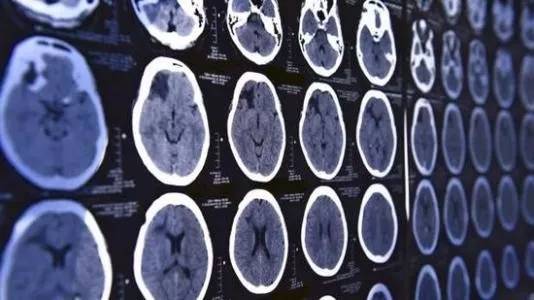

脑电图在癫痫的诊断与治疗中扮演着至关重要的角色。癫痫是由大脑神经元异常放电引起的,而脑电图能够记录这种放电现象,为癫痫的诊断和鉴别诊断提供重要依据。通过脑电图检查,医生可以判断患者是否为癫痫,并进一步确定癫痫的发作类型,从而选择合适的药物进行对症治疗。

定期复查脑电图的意义在于,它能够及时准确地把握病情变化。如果患者病情出现变化,如发作频率或发作形式的变化,通过及时复查脑电图,医生可以准确了解这些变化,从而调整治疗方案,确保治疗效果。此外,脑电图检查还可以帮助医生判断何时减药或停药,降低癫痫复发的风险。

对于难治性癫痫患者,脑电图在术前评估和手术定位中也发挥着不可替代的作用。通过多次复查脑电图,医生可以明确癫痫灶的定位,为手术治疗提供重要参考。

那么,多久复查一次脑电图合适呢?修玉香主任指出,癫痫是一种慢性疾病,如果没有特殊变化,患者半年到一年做一次脑电图复查即可。当然,如果病情有明显变化,患者应及时进行脑电图检查,以便医生及时了解病情变化并调整治疗方案。